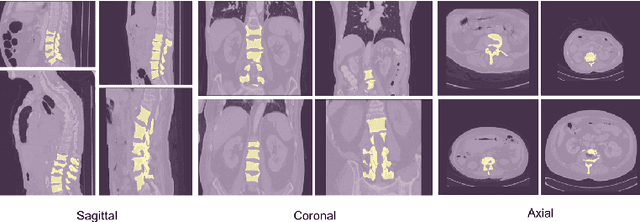

Accurate segmentation of the vertebra is an important prerequisite in various medical applications (E.g. tele surgery) to assist surgeons. Following the successful development of deep neural networks, recent studies have focused on the essential rule of vertebral segmentation. Prior works contain a large number of parameters, and their segmentation is restricted to only one view. Inspired by DoubleU-Net, we propose a novel model named DoubleU-Net++ in which DensNet as feature extractor, special attention module from Convolutional Block Attention on Module (CBAM) and, Pyramid Squeeze Attention (PSA) module are employed to improve extracted features. We evaluate our proposed model on three different views (sagittal, coronal, and axial) of VerSe2020 and xVertSeg datasets. Compared with state-of-the-art studies, our architecture is trained faster and achieves higher precision, recall, and F1-score as evaluation (imporoved by 4-6%) and the result of above 94% for sagittal view and above 94% for both coronal view and above 93% axial view were gained for VerSe2020 dataset, respectively. Also, for xVertSeg dataset, we achieved precision, recall,and F1-score of above 97% for sagittal view, above 93% for coronal view ,and above 96% for axial view.